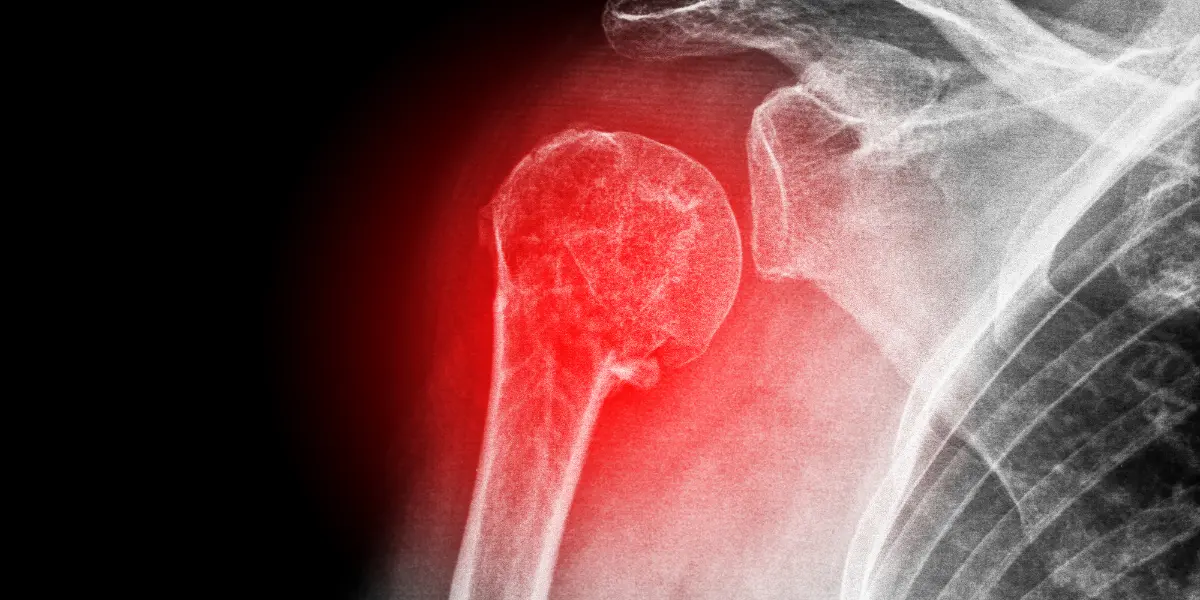

A articulação do ombro é uma das mais complexas do corpo humano, composta por três ossos principais: úmero, escápula e clavícula.

O úmero proximal conecta-se à escápula através de uma superfície articular única, enquanto a clavícula atua como suporte para os movimentos.

Essa configuração explica por que traumas simples podem gerar múltiplos fragmentos ósseos, especialmente em quedas com impacto direto.

Fraturas na extremidade superior do úmero representam 80% dos casos, segundo estudos. Já as lesões na escápula são raras, ocorrendo principalmente em acidentes de alta energia. Cada tipo de quebra altera a biomecânica articular de forma distinta, exigindo avaliação individualizada.